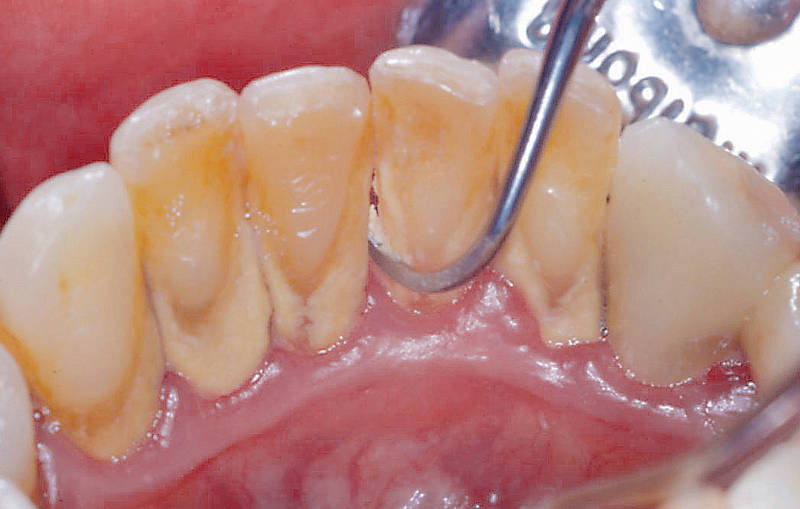

Gingivectomía

Procedimiento quirúrgico que elimina el exceso de tejido de las encías por razones estéticas, para corregir una sonrisa gingival, o para eliminar bolsas periodontales debido a la acumulación de placa bacteriana, en casos donde el hueso no está afectado.

Se realiza bajo anestesia local y se retira el tejido gingival excedente con herramientas quirúrgicas